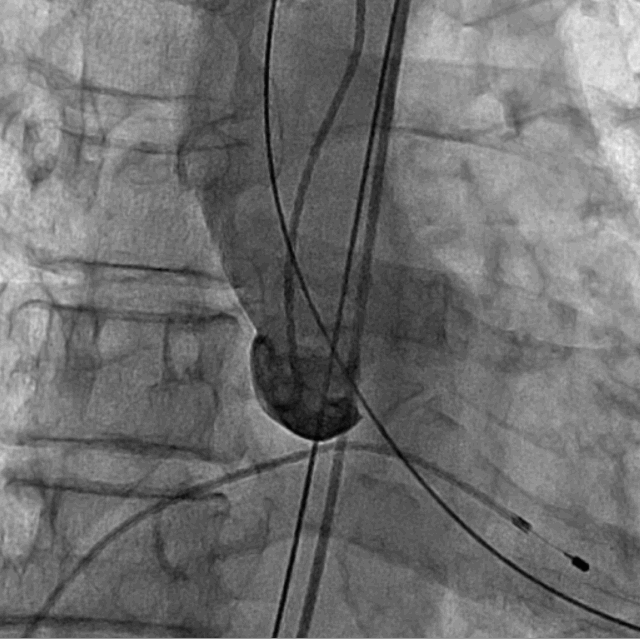

术前DSA造影

手术采用经心尖入路,对患者进行全麻后,在左侧心尖处微创手术切口仅3-4cm,在DSA及超声引导下植入JS-TAVI29#牛心包瓣膜,手术顺利完成。术前升主动脉根部测压86/47mmHg,左室压91/9mmHg,术后升主动脉根部测压87/49mmHg,左室压98/10mmHg。从导入器械到完成瓣膜置入,耗时9分钟。术后即刻主动脉瓣返流程度由术前大量返流转为消失,术后测得跨瓣峰值流速1.8m/s,平均跨瓣压差6mmHg,峰值跨瓣压差12mmHg。